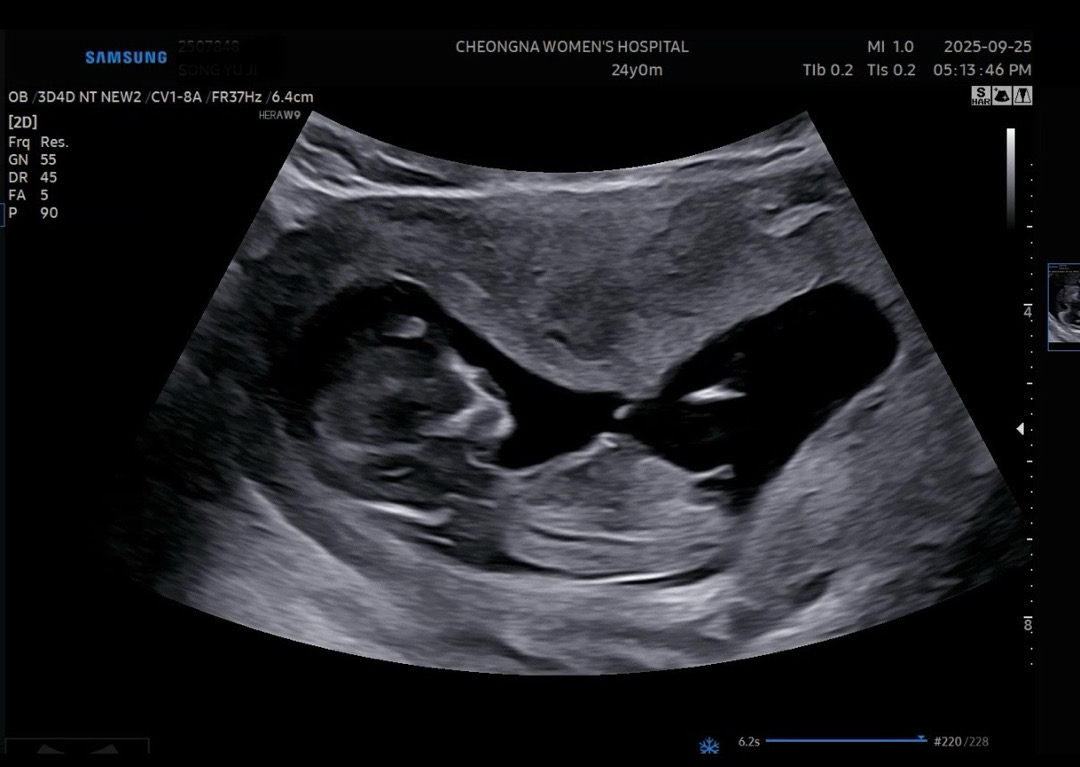

각도법 봐주세요 🌶️🍑

12주 초음파에요 ! 이제 13주인데 아직 3주나 기다리려니 이게뭐라고 ㅋㅋㅋ 은근 애간장 타네용 재미로 봐주세요 ! 여러분의 의견 궁굼합니다 🤭💗